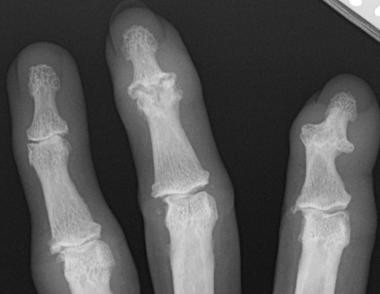

Osteoartritis je bolezen, pri kateri prihaja do vnetja sklepne ovojnice, razgradnje sklepnega hrustanca in drugih patoloških sprememb na sklepih. Je eden izmed najpogostejših razlogov za invalidnost po vsem svetu, a zanj učinkovite terapije še ni na voljo. Dejavniki, ki vplivajo na pojav osteoartritisa, so denimo nestabilnost sklepov, poškodbe in staranje. Dosedanje raziskave so že pokazale, da imajo pri nastanku osteoartritisa pomembno vlogo proteini MMP3, MMP13 in ADAMTS5. Gre za encime, ki razgrajujejo zunajcelične proteinske komponente hrustanca.

Znanstveniki in znanstvenice so najprej analizirali izražanje genov v vzorcih tkiva bolnikov in modelnih miši z osteoartritisom. Rezultati so pokazali, da je v obolelem hrustančnem tkivu močno povečana izraženost proteina ERRγ. Nato so v gojene zdrave hrustančne celice ter v zdrave miši vnesli genski konstrukt za izražanje proteina ERRγ in spremljali spremembe na hrustancu. Povečano izražanje proteina ERRγ je povzročilo pojav simptomov osteoartritisa, torej razgradnjo hrustanca, vnetje sklepne ovojnice in nastanek izrastkov na kosteh.